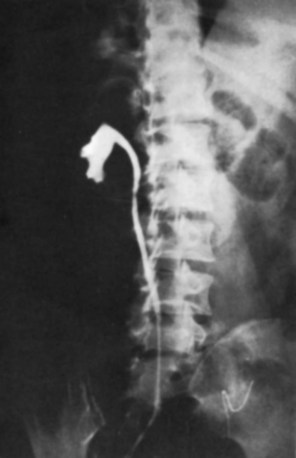

The majority of cases will show positive findings on excretory urography, the most common findings being hydrocalycosis, hydronephrosis, or hydroureter due to stricture formation (Wang et al, 2003). Early signs include the moth-eaten appearance of calyceal erosion and papillary irregularity. These signs are best seen on early excretory films, because they are often masked by increasing density of the contrast on later films of the IVU. Cavitary lesions communicating with the collecting system are characteristic of TB. These lesions eventually enlarge as parenchymal destruction ensues, and a picture similar to chronic pyelonephritis may be seen. Fibrotic distortion of the collecting system and ureter is also seen. Calyceal obliteration and amputation, hydrocalycosis, segmental or total hydronephrosis, and a shriveled reduced-capacity renal pelvis may all be signs of renal tuberculosis (Figs. 16-2 and 16-3). Scarring and angulation of the ureteropelvic junction (UPJ) may also occur, the so-called “Kerr’s kink” (Matos et al, 2005). Ultimately diminished or absent function and extensive calcification may be seen with autonephrectomy. If nonvisualized on IVU, the kidney is best evaluated by computed tomography (CT) or ultrasonography.

Tuberculosis of the ureter is commonly seen as a rigid, straightened “pipe-stem” ureter. A beaded, corkscrew appearance is sometimes also seen. Ureterovesical junction obstruction is caused by tuberculous cystitis or strictures of the distal third of the ureter (Fig. 16–4). Secondary stone formation on top of this stricture is an occasional finding. The cystogram films may show a small contracted bladder due to excessive fibrosis (Fig. 16–5). Of note, although IVU is being phased out by CT-urography in many developed countries (Stacul et al, 2008), IVU continues to be a reliable imaging modality for genitourinary TB in most parts of the world.